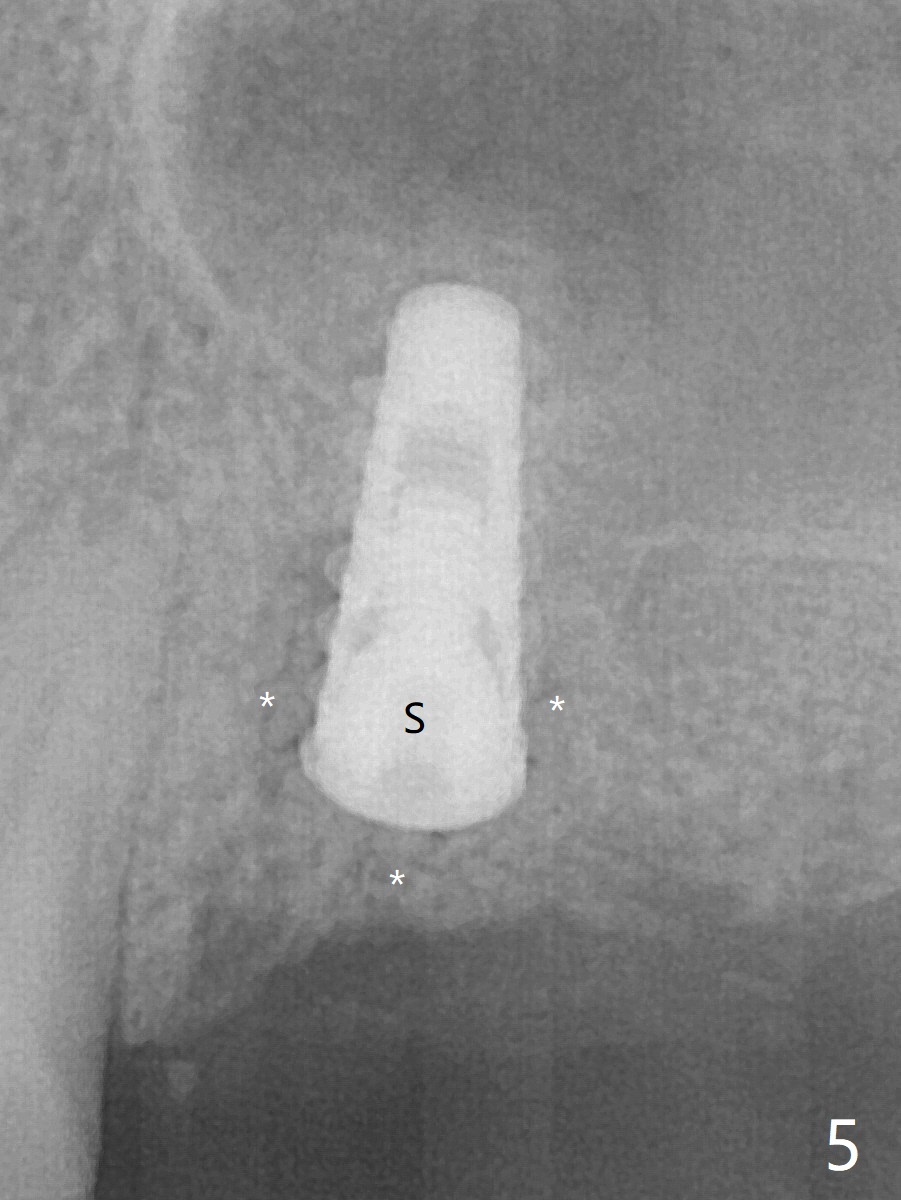

Five months post implant removal and bone graft, incision is made at #12. Osteotomy is being done with guide until 3.0x7.3 mm drill with 1 O-ring (palatal wall being thin), followed by 3.2x17-19 mm sinus round drills and 2.2x11.5 mm drill. After placement of 2 small loads of bone graft, a 4x9 mm dummy implant is inserted for sinus lift (Fig.1,2 *). By this time, the buccal plate is gone, while there is apparently the palatal periosteum. With more bone graft for sinus lift, a 4x9 mm final implant is placed with 30 Ncm (machine) and 4 mm subgingival (Fig.3,4 double arrows). Sticky bone (Fig.5,6 *) is applied around the coronal end of the implant and cover screw (S), followed by 2 pieces of PRF and 4-0 PGA suture. The sutures appear to have been dissolved and PRF membrane exposed 7 days postop (Fig.7,8 (smoker)). Four months postop, the wound heals except a small hole, which seems to be communicated with the underlying implant (Fig.9). The sinus lift remains (Fig.10 <), while bone loss appears to be present around the implant (Fig10,11 *). After placement of 5.5x4 mm healing abutment and before suturing, allograft is pushed into periimplant space (Fig.12, 13 *).